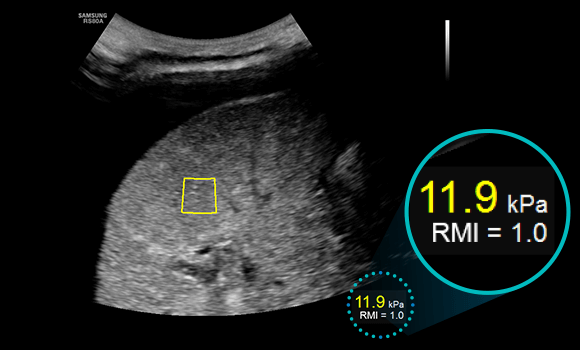

S-Shearwave

S-Shearwave detects the velocity of the shearwave propagated through the targeted lesion and displays the numerical measurement of stiffness In kPa or m/s together with a Reliable measurement Index (RMI)*. S-Shearwave has the potential to reduce the number of conventional liver biopsies by providing quantitative tissue characteristic information.